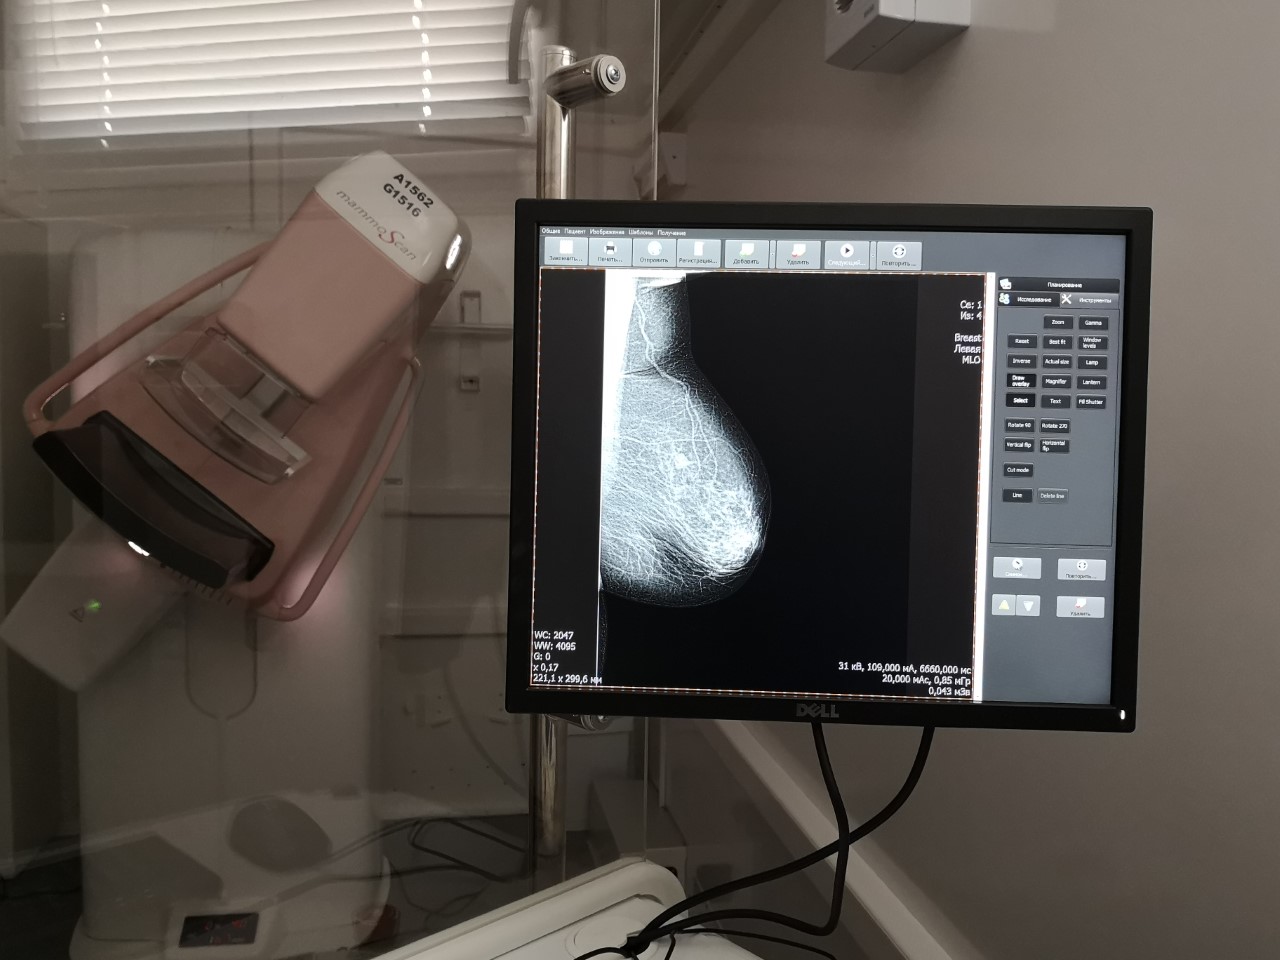

Cancerul continuă să fie maladia despre care mai mult se șoptește, decât se vorbește, pentru că este un diagnostic care inspiră groază, suferință și neputință. Din frică și prejudecata că maladia te duce în cimitir, moldovencele sunt sceptice când vine vorba să se palpeze, să facă o ecografie sau o mamografie a sânilor. La Criuleni, acolo unde am găsit unul din mamografele mobile, femeile așteptau în rând cu emoții, dar și cu frică să nu cumva să fie ceva.

În cele patru zile de când mamograful mobil a venit în Criuleni, 123 de femei au făcut o mamografie. Aproximativ 30 de radiologii se pot face pe zi, ne explică tehnicianul.

„Inginerul ne-a spus că mai mult de 30, poate 31 pe zi nu se fac. Se

blochează calculatorul, pentru că așa este făcut sistemul. Avem 3 mașini în

teritoriu, câte 30 de oameni în fiecare zi, deci noi în fiecare zi facem 90 de

radiologii în teritoriu. La Institutul Oncologic au rămas alți doi tehnicieni,

care citesc aceste radiologii, așa că pentru aceste femeii vor fi rezultatele

într-o lună, o lună și jumătate. Dacă găsesc un caz grav ei îl anunță repede”,

afirmă tehnicianul Liudmila Annenkova.